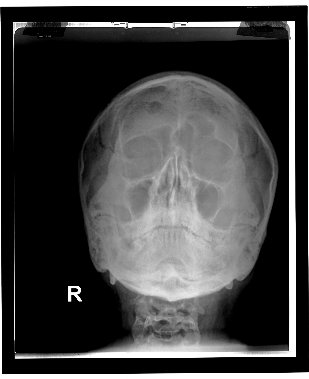

IDD digitizers produce exceptional quality film and paper images.

To download DICOM sample images, click here.

To download JPEG sample images, click here.